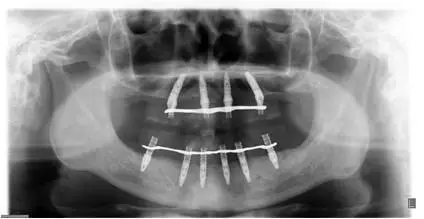

患者男性,51歲,全口無(wú)牙,下頜骨量尚可,上頜后牙區(qū)上頜竇底剩余骨高度嚴(yán)重不足,前牙區(qū)牙槽突較豐滿,主訴希望全口種植固定義齒修復(fù)。于2015年 9月接受種植治療:上頜采用All-on-4種植方案、下頜采用常規(guī)種植6顆種植體方案,種植后行即刻修復(fù)(圖1-2)。